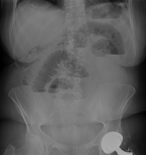

Diverticulitis of isolated jejunal diverticulum complicated by small bowel obstruction secondary to de novo enterolith formation

Ivan O Aispuro and Nazhone P Yazzie

Journal of Surgical Case Reports, Volume 2019, Issue 5, May 2019, rjz151, https://doi.org/10.1093/jscr/rjz151